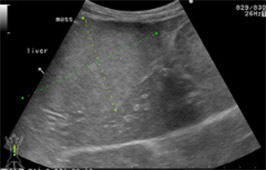

腹部超音波検査およびCT検査にて右副腎に直径6cm大の腫瘍(赤矢印)が認められました。機能性副腎腫瘍が疑われ、飼い主様の希望により摘出手術を行いました。